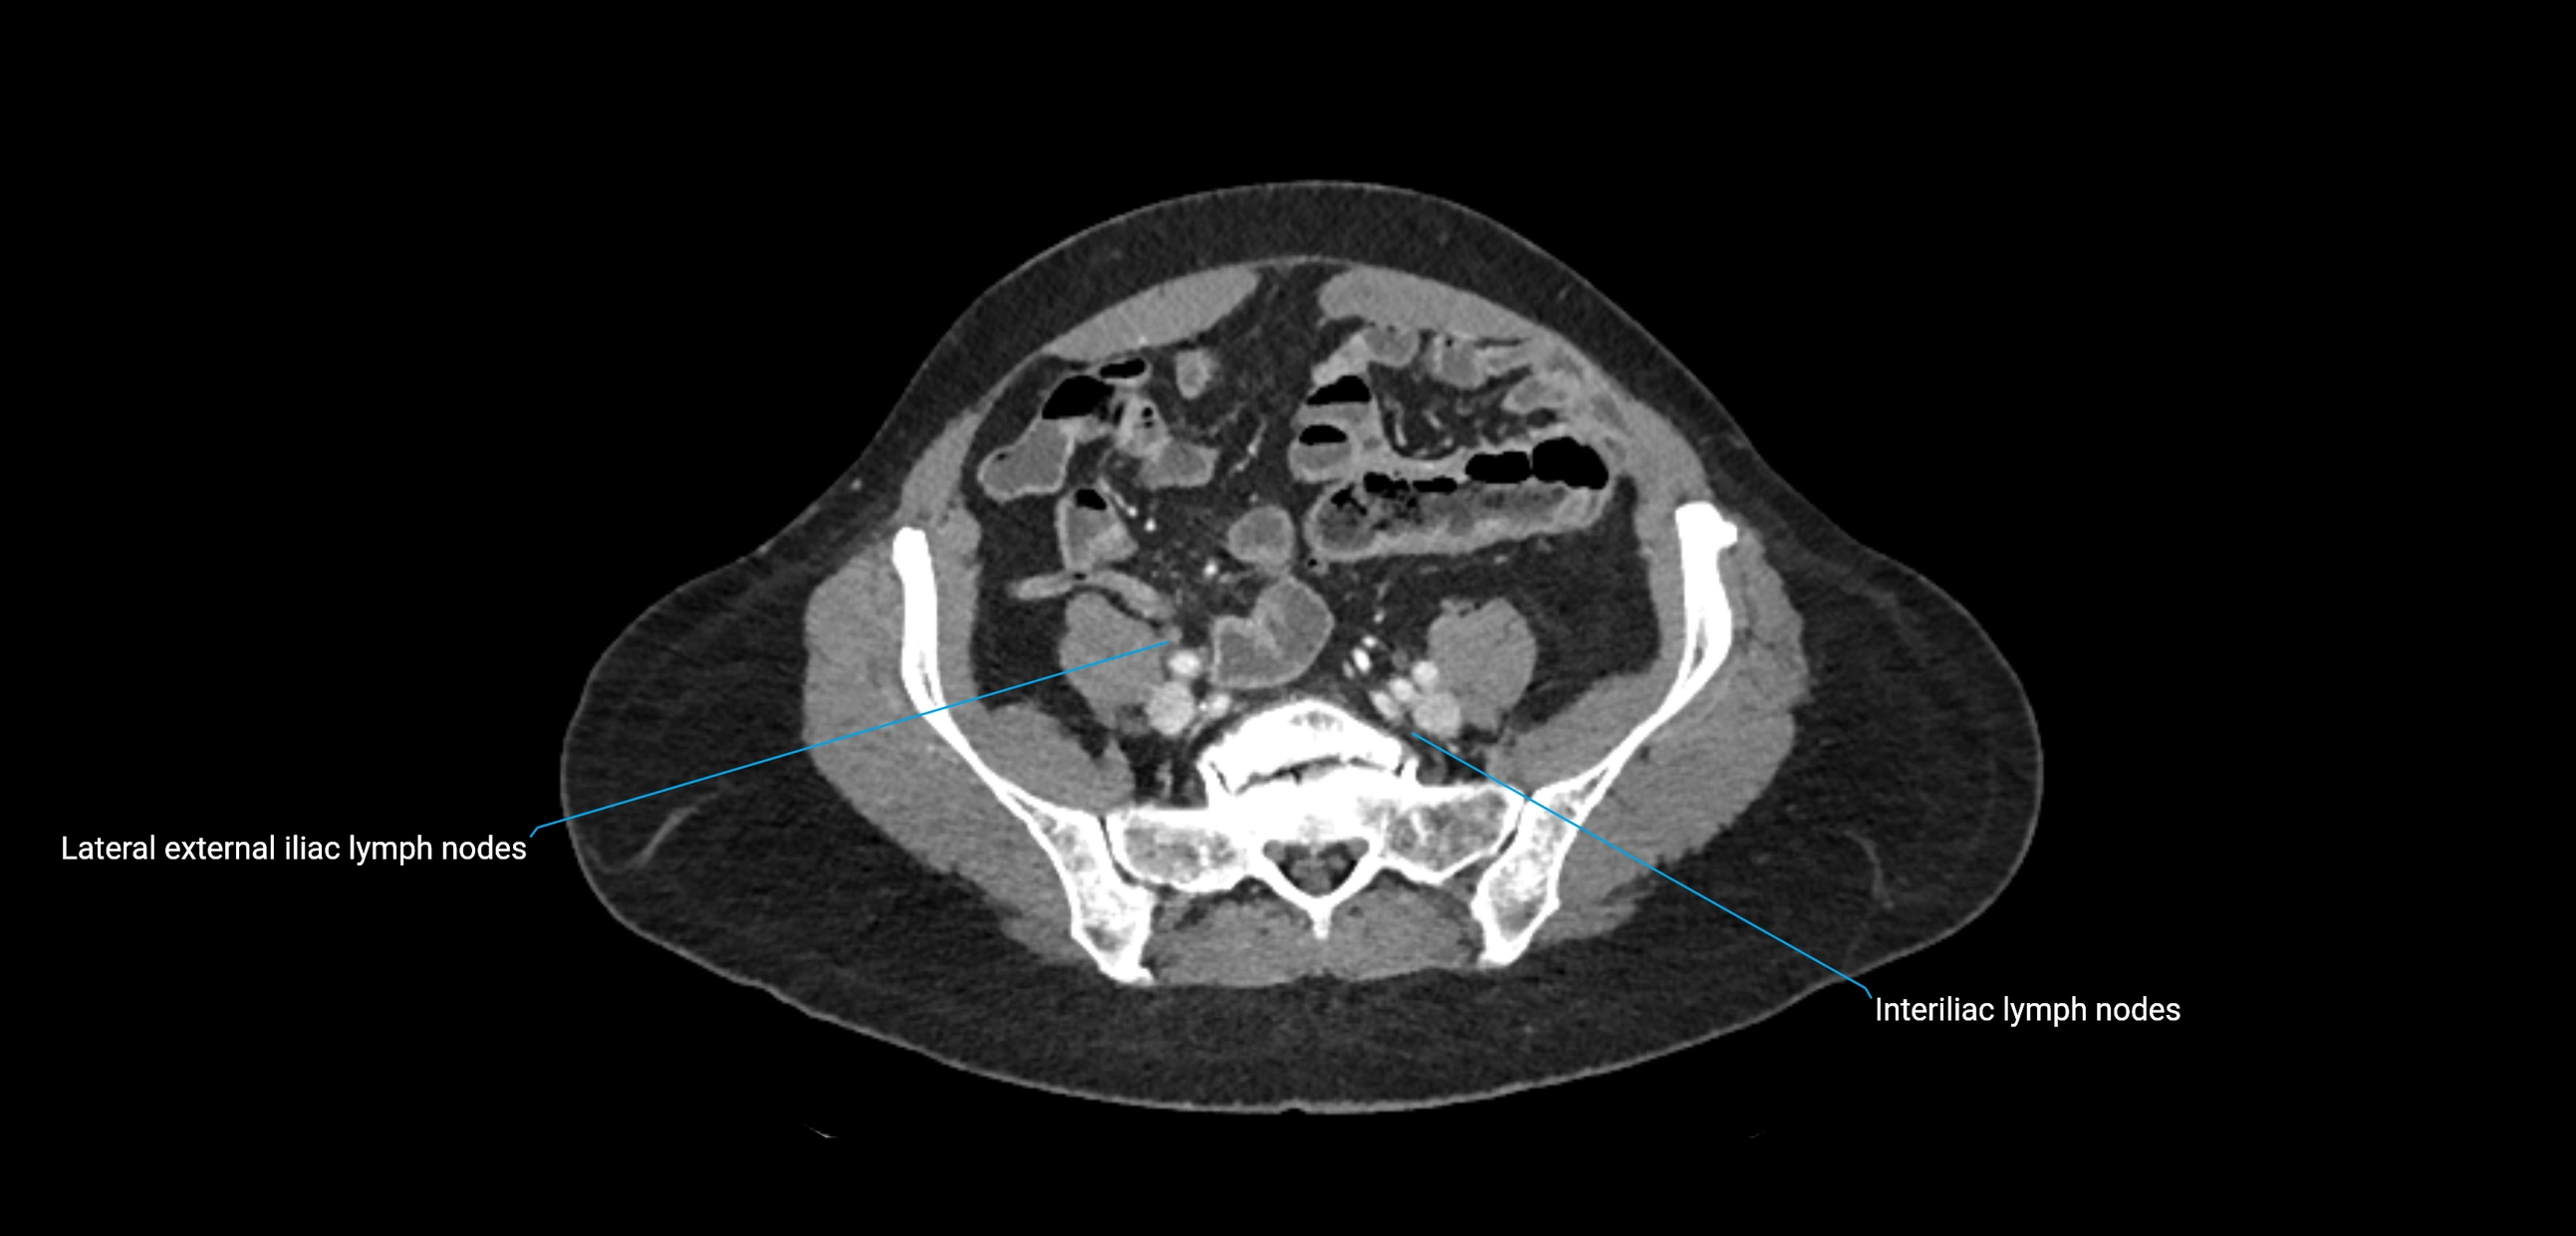

CT image

image